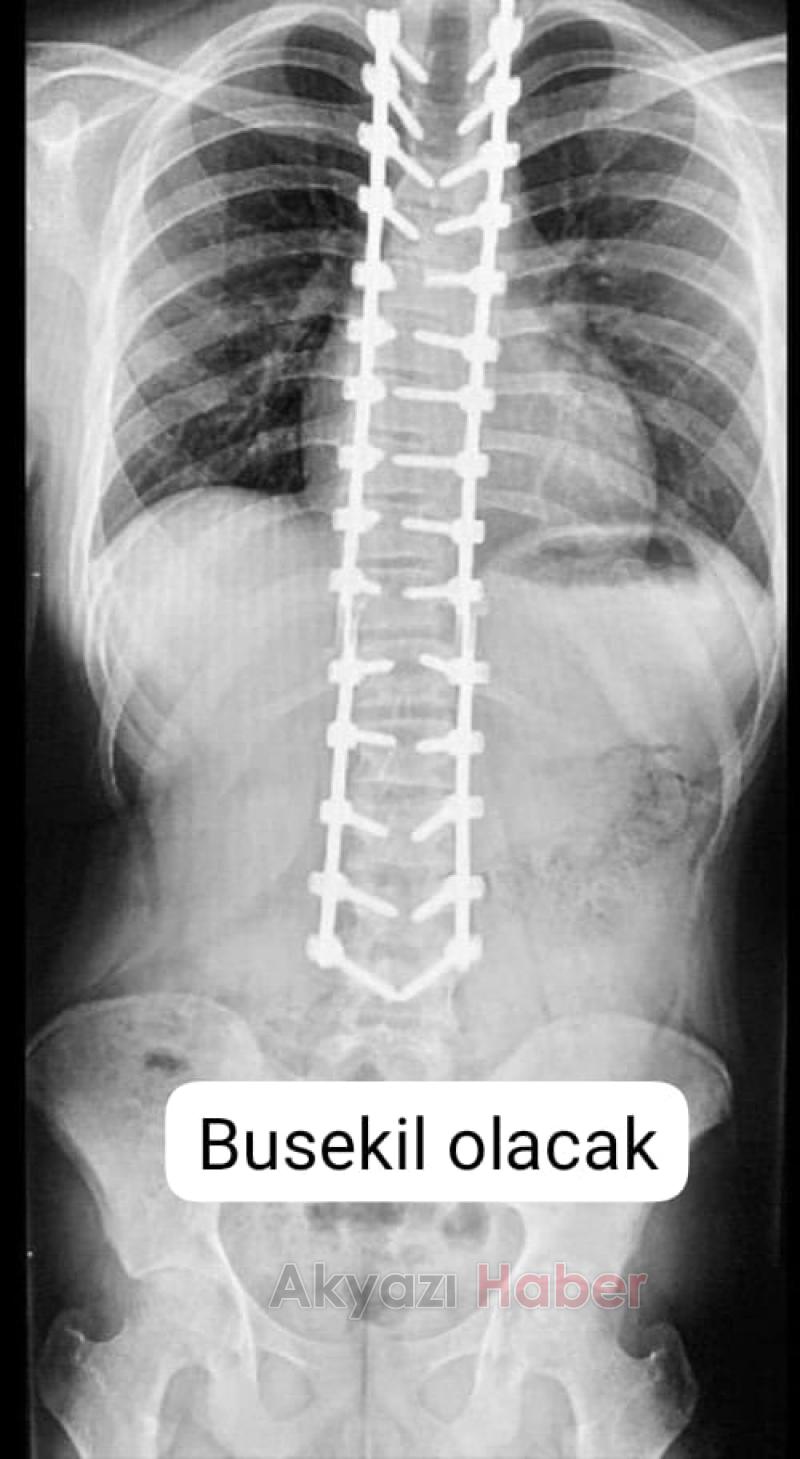

Skolyoz hastası Ecrin Selim'in ameliyatı için gerekli olan 125 bin lira için ailesi hayırsevelerden yardım çağrısında bulundu.